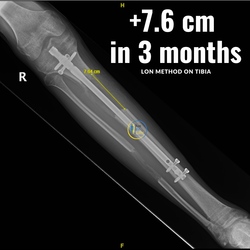

With the combined method (Lon method), an internal nail and an external fixation are attached which allow the bone to be extended from the outside.